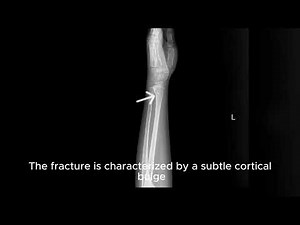

Fracture - Greenstick